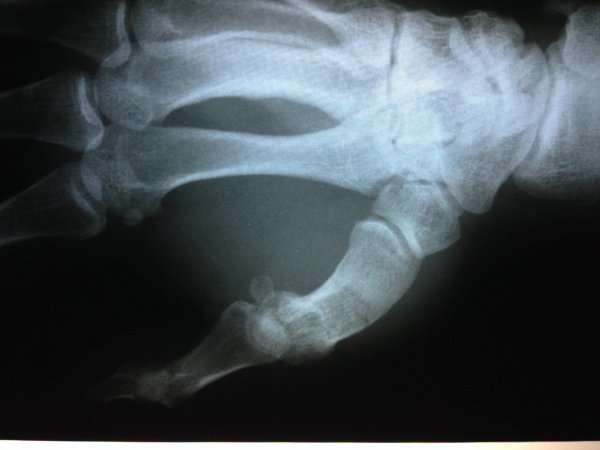

DOKUMENTACJA MEDYCZNA GAMROTA I WŁODARKA

Dokumenty dotyczące kontuzji zawodników KSW.